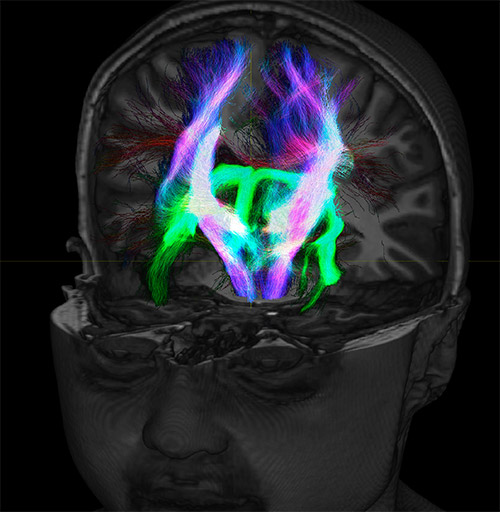

Fiber tractography of the corticospinal tract with seed region of the posterior limb of the internal capsule. Different processing based on the same data.

All images were created from the same acquisition in a child using Ingenia 3.0T CX and 32-channel dS Head coil. Diffusion data was acquired at b-values 0, 500, 1000, 2000, 3000. The use of high b-values (3000 s/mm2) effectively suppresses extra-axonal water signal and provides high angular resolution.

Super-resolution directionally encoded color track-density imaging overlaid on T1-weighted structural MRI.